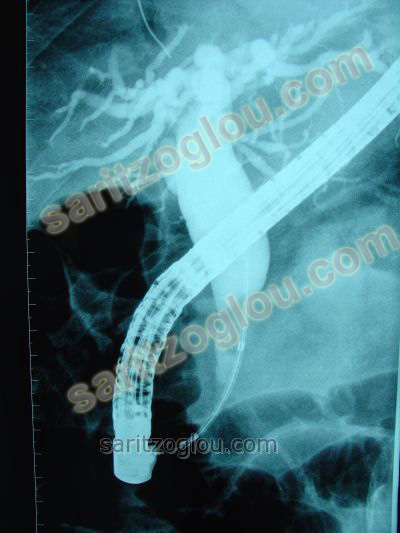

Στον προηγούμενο ασθενή, τοποθετήθηκε stent στον χοληδόχο πόρο προκειμένου να αποφευχθεί η πλήρης στένωση του πόρου και η εμφάνιση ίκτερου. Στην συγκεκριμένη περίπτωση ο ασθενής υποβληθεί σε χειρουργική επέμβαση παγκρεατεκτομής.

Στην πρώτη εικόνα φαίνετε μεγάλη στένωση του κατώτερου τμήματος του χοληδόχου πόρου λόγω διήθησης από νεόπλασμα της κεφαλής του παγκρέατος. Στην δεύτερη και τρίτη εικόνα φαίνετε η τοποθέτηση μεταλλικού stent με το οποίο αποκαθίσταται η βατότητα του πόρου.

Στον προηγούμενο ασθενή τοποθέτηση μεταλλικού stent με το οποίο αποκαθίσταται η βατότητα του πόρου.